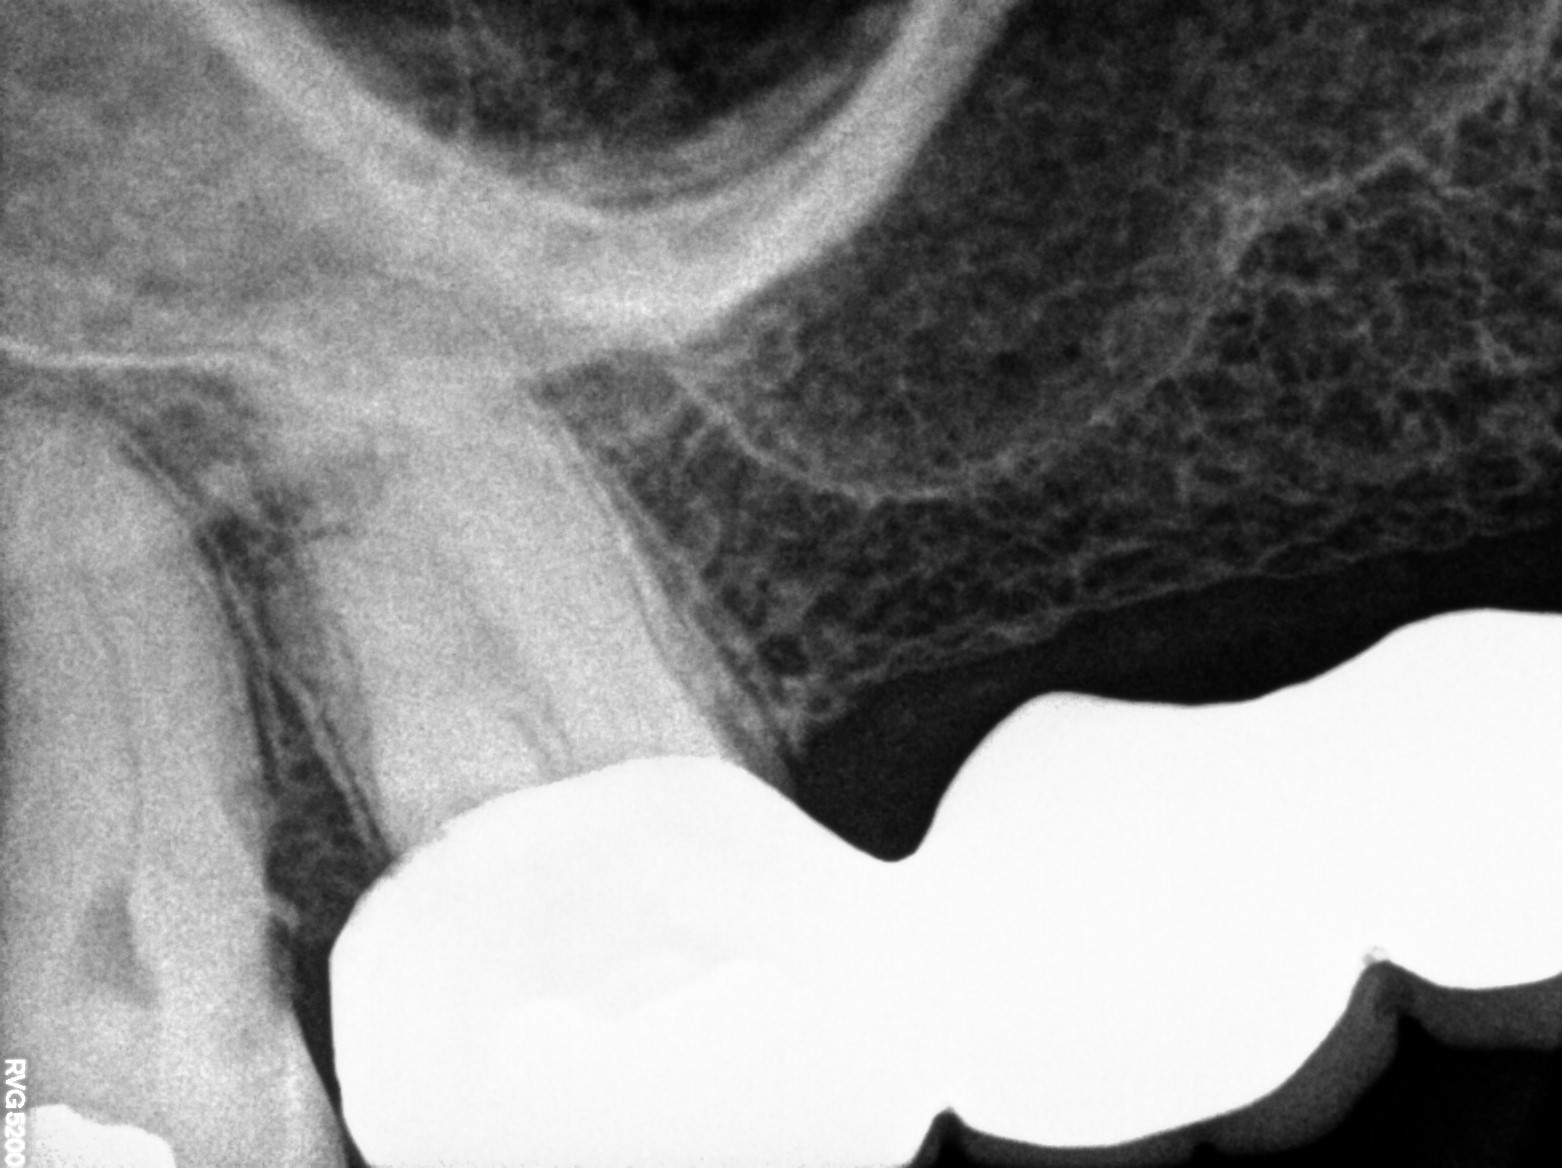

Dental Radiographs FHIR: DocumentReference · LOINC 24641-7

xray_1764234367_1.jpg

24641-7